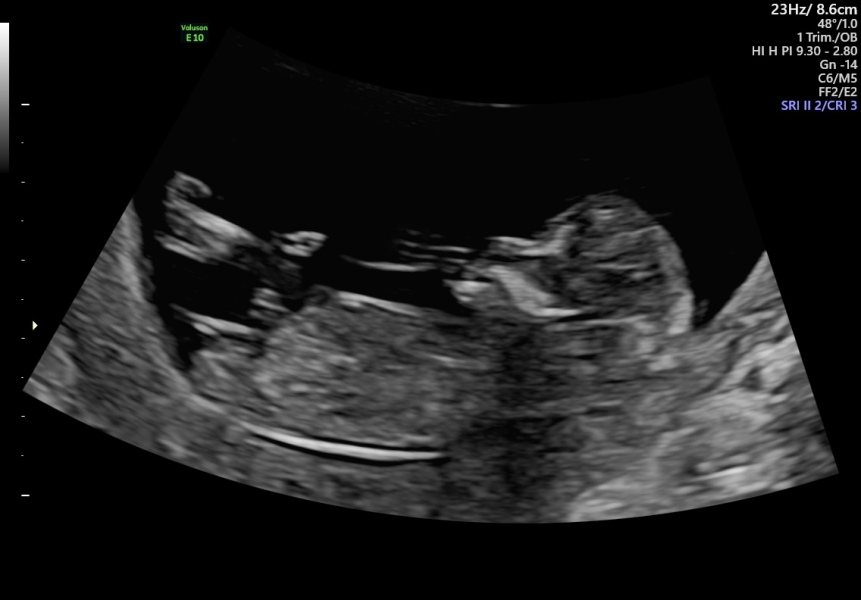

Hi ladies! Coming from thread 2. Had my 12 week scan today! Oh my god, baby would not stop wiggling! After laying on either side several times, lots of wiggling, emptying partially then full bladder, and a 20 minute walk with a fizzy drink, baby would still not cooperate😂. Got measurements but unfortunately couldn't do the screening, so I will be having some bloods done at 16 weeks for it. But baby is healthy! Due the 15th March, a day ahead of what we thought. Very long legs, longer than my daughters at this stage.

NHS dating scan today which bumped me forward to bang on 13 weeks and new due date 13th March! Having an elective section so guess baby will arrive the week before 😍